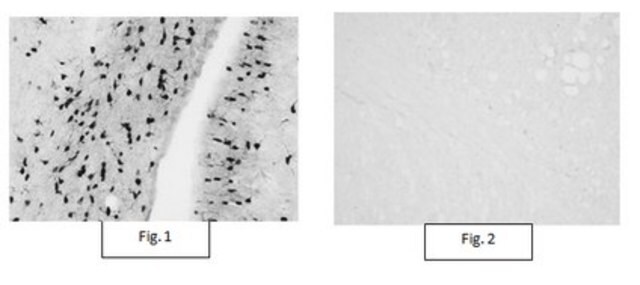

免疫组化分析:一个代表性批次使用自由漂浮的小鼠脑切片在胼胝体/外囊中检测到Aspa/Nur7阳性少突胶质细胞(由Dr. John R. Moffett, Uniformed Services University of the Health Sciences提供)。

免疫组化分析:代表性批次在大鼠前脑的不同区域检测到Aspa/Nur7表达模式,包括胼胝体、大脑皮层、海马连合(hc)、菌毛和前连合(Madhavarao, C.N., et al. (2004).J Comp Neurol.472(3):318-329)。

免疫组化分析:代表性批次在大鼠前脑的不同区域中检测到与CC1相似的Aspa/Nur7表达模式,包括小脑、胼胝体的Purkinjie&轴突纤维层以及初级躯体感觉皮质的第2层(Madhavarao, C.N., et al. (2004).J Comp Neurol.472(3):318-329).